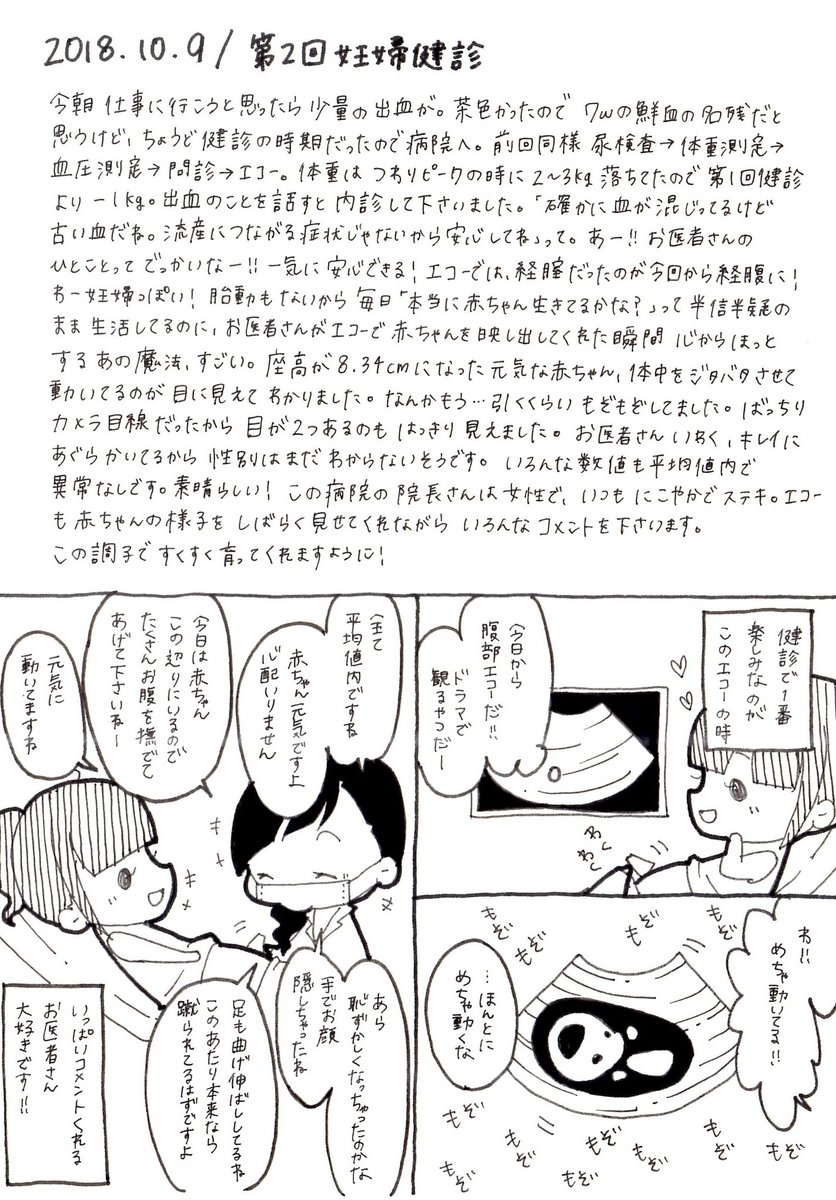

2018.10.9 第2回妊婦健診! 動いている姿が見られると、本当に私の中で生きてるんだー!って思えます。 1度は流産と言われた赤ちゃん、もう心配いらないとのこと!良かった…! #育児漫画 #育児日記 #妊娠 #妊娠初期 #妊婦健診 #エコー #妊娠3ヶ月 #イラスト好きさんと繋がりたい #オリジナル漫画 pic.twitter.com/Pipsmdyuop

2019-08-17 22:19:54 拡大

拡大

拡大

拡大